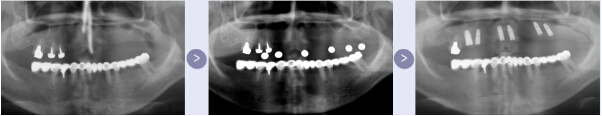

二、植入人工种植体

在局麻的状态下,将种植体植入患者的牙槽骨内。通常植入一枚需要10-30分钟。如缺牙部位骨量不足,则需植入人工骨粉材料进行补充。种植完成后,患者需要等待人工牙根和牙槽骨结合,大致需要2-6个月,这段时间可戴临时假牙度过。

植入种植体

三、烤瓷冠修复

人工牙根和牙槽骨完全结合后,就可着手种植体的牙冠修复,这一过程大约用时一个月。后修复完成后,患者还需定期复查,以维护种植牙的长期使用。

人工牙冠修复